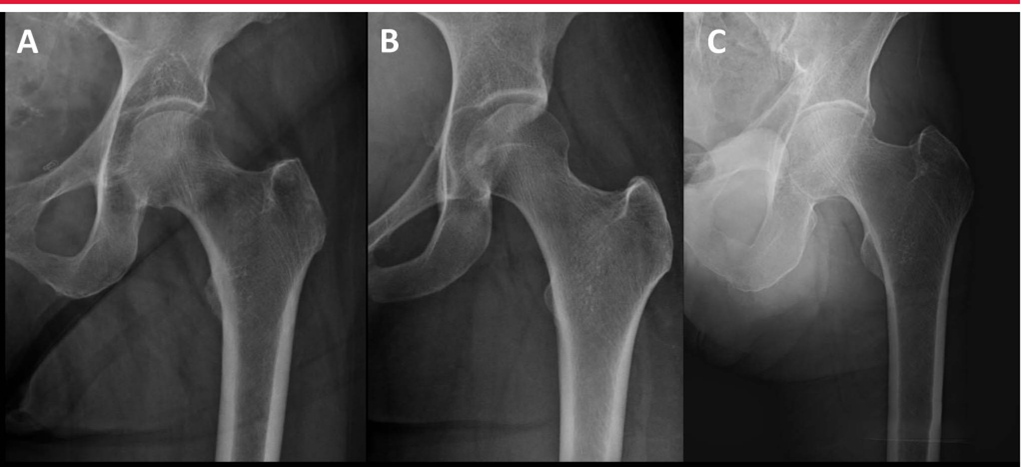

Для оценки морфологии перелома необходима специализированная рентгенография бедра. Хотя взаимосвязь между кончиком большого вертела и центром головки бедренной кости обычно копланарная, переднезадняя рентгенограмма таза или контралатеральная рентгенограмма бедра может помочь оценить нативную анатомию и потенциальный вальга-тазик или варум тазика (coxa vara) (нормальная диафиз шейного отдела). угол на картинке ниже, B coxa valgus, C coxa varus)